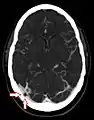

- Angiografía por TC que muestra una granulación aracnoidea en el seno transverso derecho

- TC sin contraste de la cabeza que muestra una granulación aracnoidea